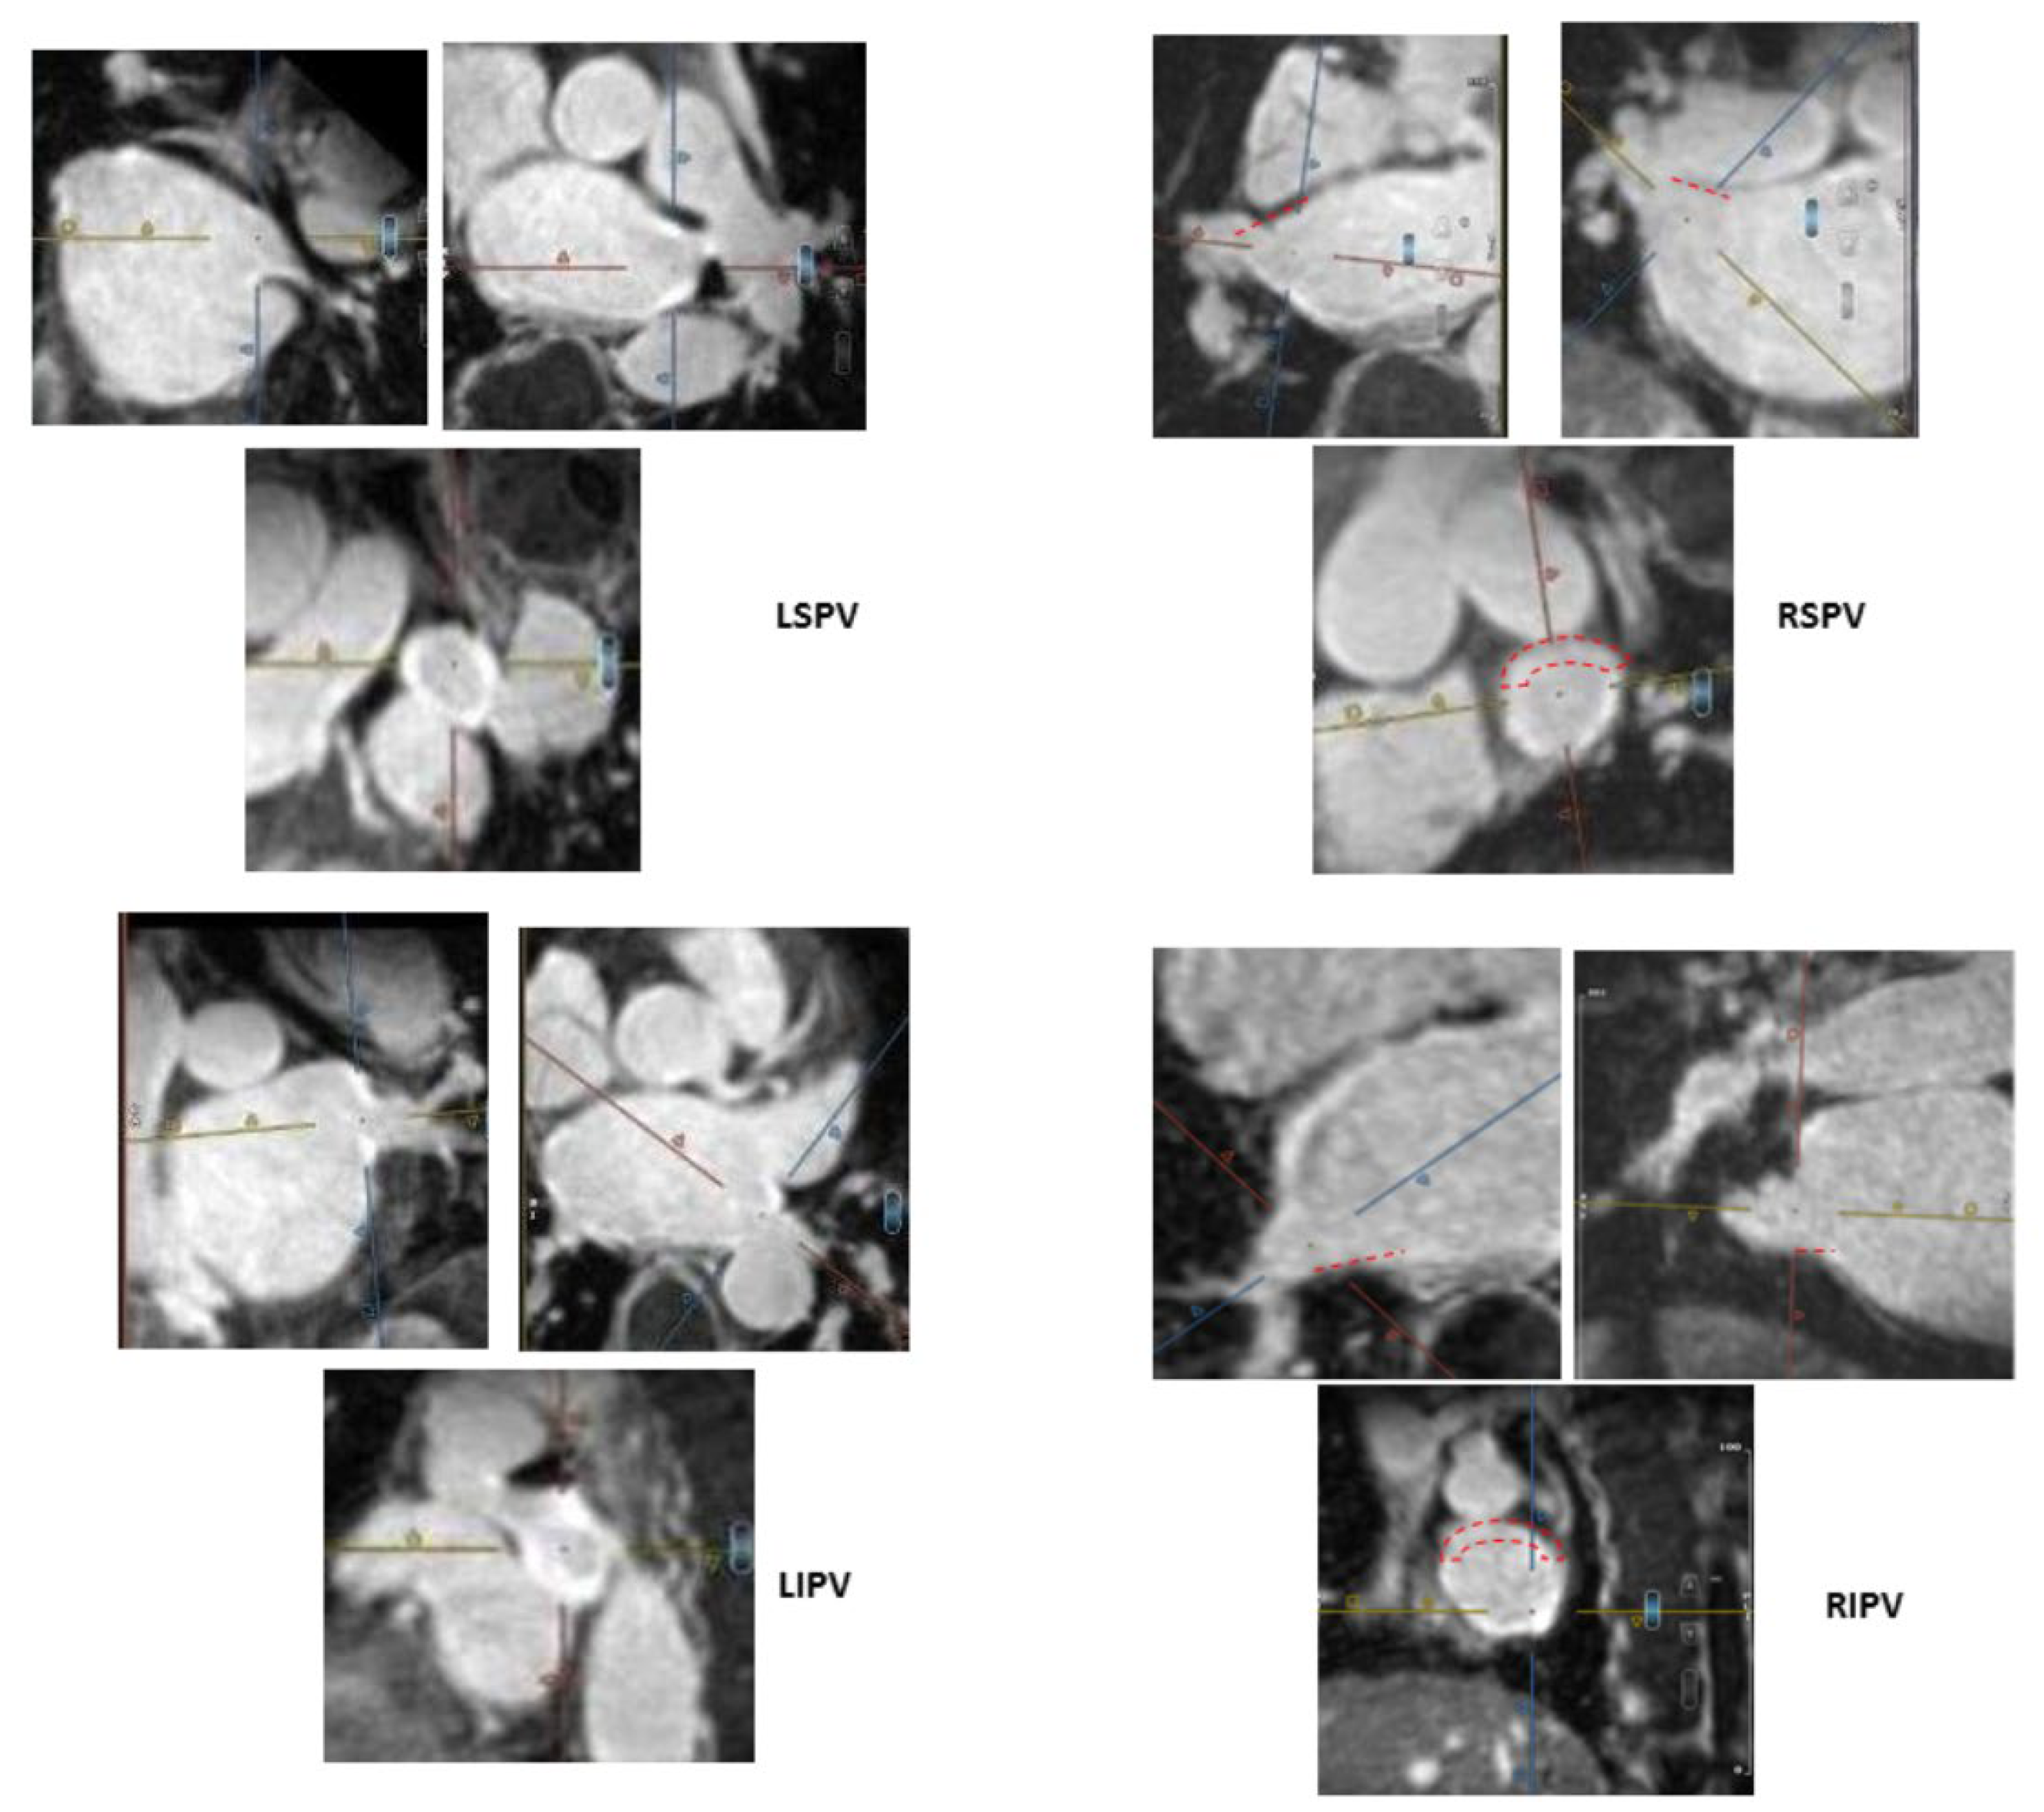

2.4. MRI Definitions and Categorization of Ablation-Induced PV Ostial Fibrosis

- −

- Complete—circumferential PV ostial LGE without gaps;

- Sub-complete—an almost circumferential LGE around PV ostium with the presence of a minor LGE gap only;

- Partial—incomplete circumferential LGE around PV ostium due to the presence of a major LGE gap;

- Absent PV fibrosis—no LGE around PV ostium.

) and thus are defined as partial incomplete circumferential PV ostial fibrosis. The right PV gaps are marked (

) both on the orthogonal plane images and the cross-sectional view.